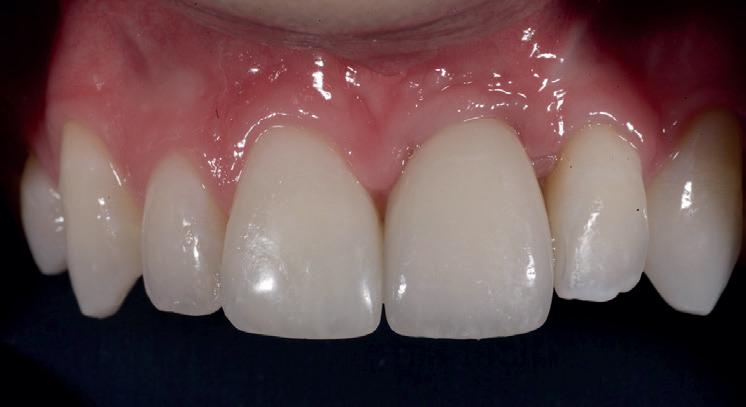

SITE AUGMENTATION Reconstituirea țesutului moale periimplantar și papilar în zona estetică

RECONSTITUIREA țesuturilor moi periimplantare. Scopul acestui raport de caz este de a demonstra procedurile chirurgicale utilizate pentru corectarea unui defect al țesuturilor moi periimplantare folosind țesutul moale interdentar în combinație cu tuberozitatea ca locație donatoare de țesut conjunctiv, utilizând o abordare prin tunelizare într-o zonă estetică.